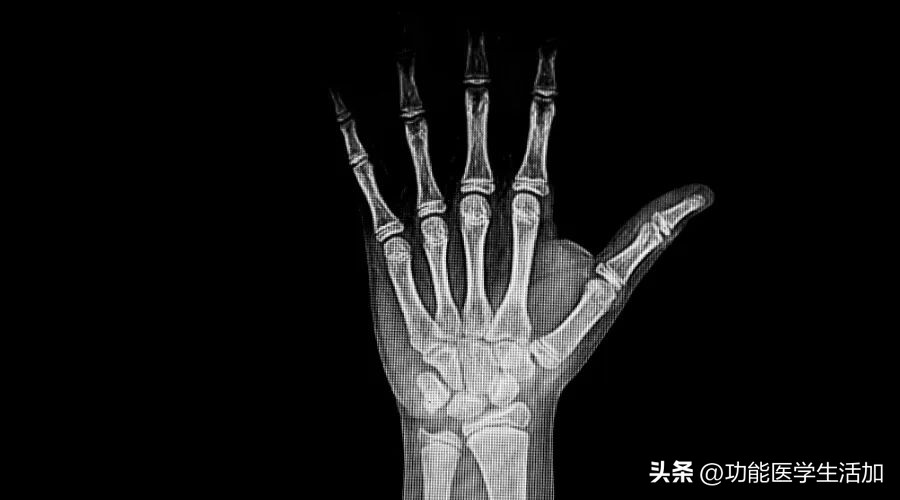

①骨龄

如果孩子身高提前出现了快速增长,家长可以带孩子到医院拍张X片(对左手骨及手腕部等部位拍摄),以有效评估骨龄情况。

如果骨龄超过实际年龄≥1岁,则意味着性早熟。